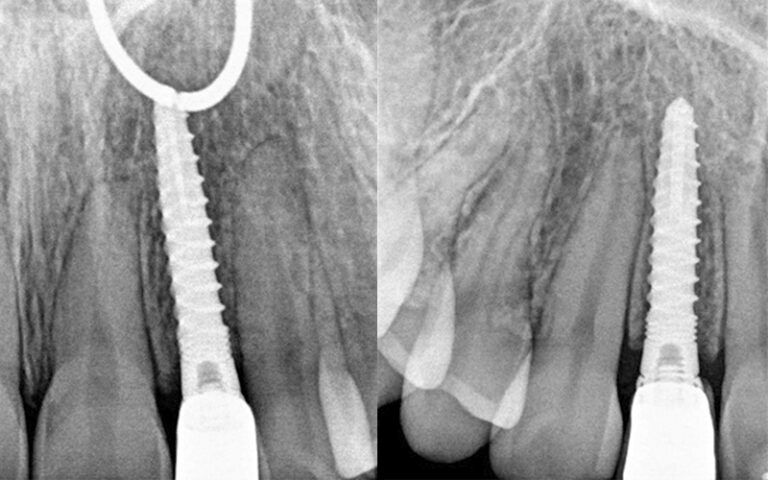

X-ray images of the revision at 6 months post-placement of the implants and 2 months after prosthetic load X-ray images of the revision at 6 months post-placement of the implants and 2 months after prosthetic load